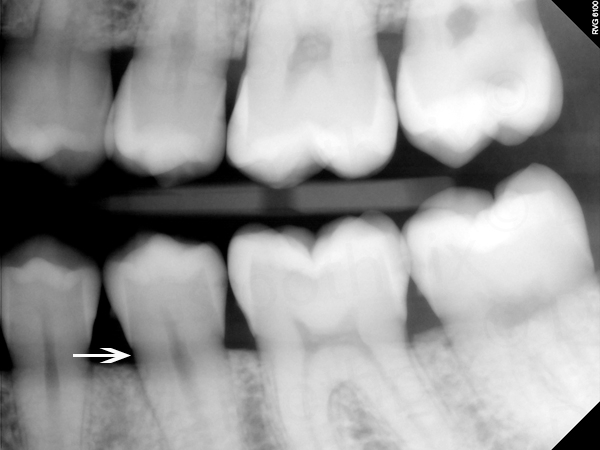

11. What is the radiolucency on the teeth # 1.1, 1.2, 1.3?

12 / 30

12. What is the condition showed by the arrow?

13 / 30